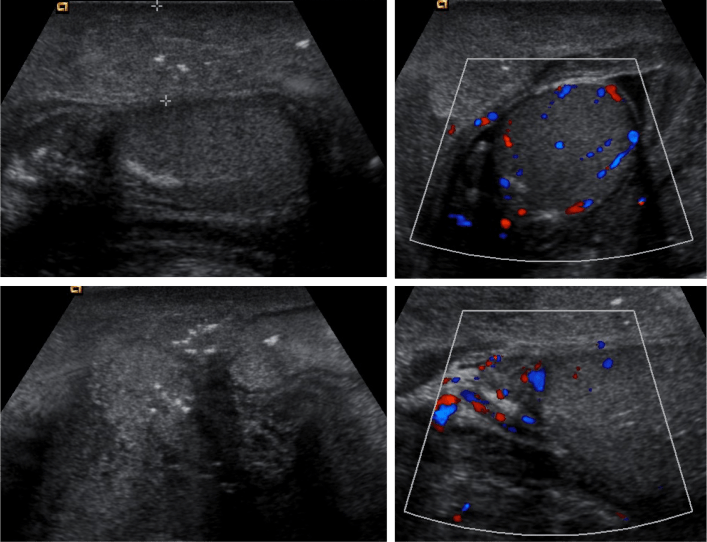

Ecografía.

La ecografía escrotal es útil para establecer el diagnóstico de GF incluso antes de la manifestación clínica y también para descartar otras entidades como la celulitis, torsión testicular, la hernia o la orquiepidimitis.

Puede existir:

- Engrosamiento de cubiertas.

- Focos ecogénicos de gas en la piel del escroto (patognomónico). Estos focos no se ven en el parénquima testicular, no confundir con calcificaciones. Una hernia puede presentar gas en la piel del escroto, pero se diferencia de la GF porque existe gas en el interior del asa de intestino obstruida, lejos de la pared escrotal.

- Epidídimo y testes de ecoestructura conservada debido a que tienen un aporte sanguíneo diferente (arterias testiculares, se originan desde la aorta).